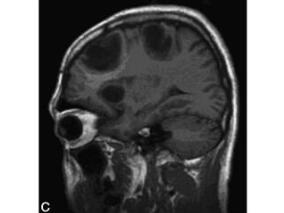

1小时条评论71岁男性,因右侧肢体无力就诊。头颅CT检查左侧基底节区可见一类圆形高密度影。活检报告显示为炎症,给予抗炎、激素治疗后,病变消失无复发。2年半后复查,头颅MRI发现右侧大脑颞叶皮质内一团块状长T1、长T2信号影。无明显主诉,给予激素治疗后,病灶明显缩小,患者...